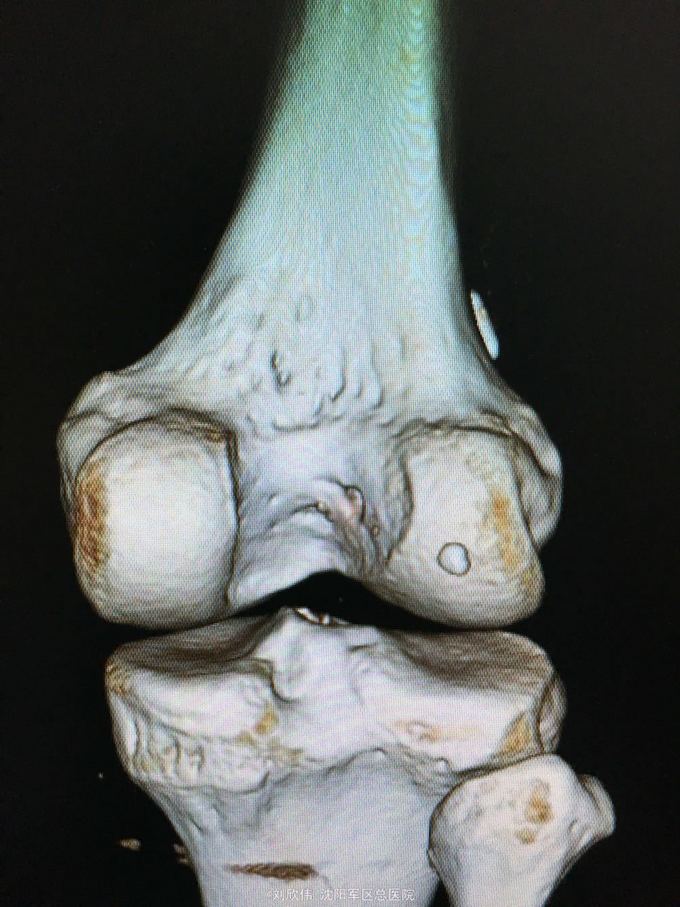

训练致右膝肿痛伴活动受限3个月 自觉脱臼感

右膝lachman试验,轴移试验阳性 MRI提示ACL已显示不清,半月板后角高信号(但术中未见撕裂,mri存在假阳性)

右膝前交叉韧带断裂 右膝半月板损伤 手术方法如题,直接上图